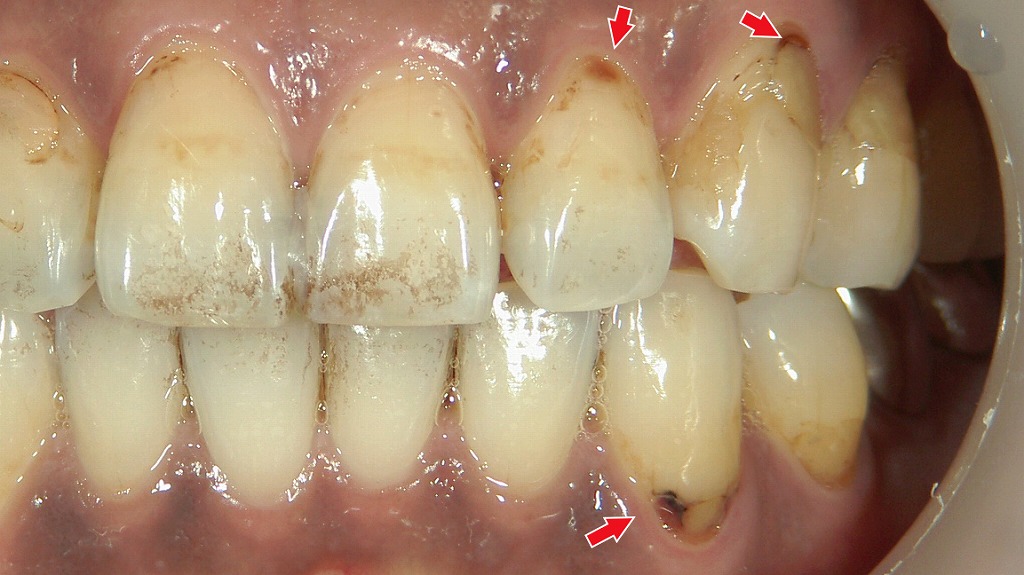

歯石の黒色化

歯の根元や歯と歯の間に付着した歯石が、唾液中の成分や細菌の代謝物、タバコのヤニなどと反応して黒く変色した状態を「縁下歯石(黒色歯石)」と呼びます。

黒色歯石は、通常の白っぽい歯石よりも硬くて強固に付着するため、日常のブラッシングでは取り除くことができません。

このタイプの歯石が見られる場合、

- 歯周病が進行しているサインであることが多い

- 歯肉の炎症や出血を引き起こしやすい

- 歯周ポケットの内部にまで及ぶことがある

といった特徴があります。

除去するには、歯科医院で行うスケーリングやルートプレーニングが必要です。黒色歯石を放置すると細菌の温床となり、歯周病が悪化する恐れがあるため、早めのケアが重要です。